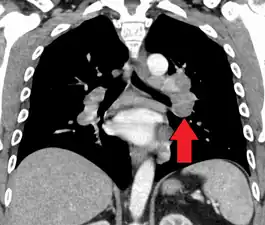

Hilar adenopathy especially on the person's left (AP CXR)

Hilar adenopathy especially on the person's left (coronal CT)